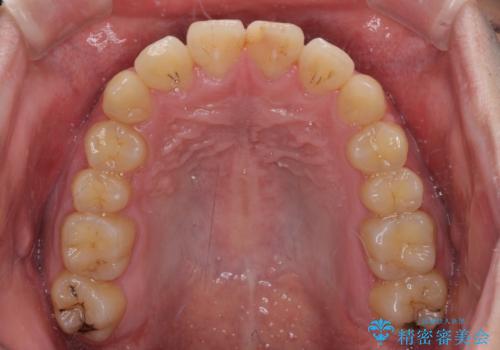

- 上下のデコボコと前歯のクロスバイトを改善したいとのことで来院された患者様です。

マウスピース矯正での自己管理には自信がないとのことで、ワイヤー装置による矯正治療を行うこととしました。

デコボコの程度は強かったのですが、口元の突出感はなかったため、非抜歯矯正としました。